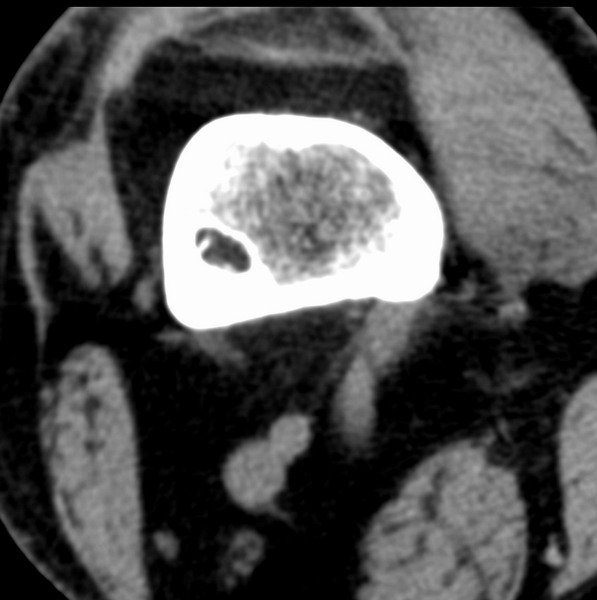

右侧膝关节疼痛一月

男、48

股骨下段、胫骨上段。

1、股骨干骺端病变考虑干骺端纤维性皮质缺损愈后(非骨化性纤维瘤)改变,胫骨近端内生骨瘤(或干骺端纤维性皮质缺损愈后改变);

2、骨关节炎,骨质增生,股骨外侧髁退变性囊肿(关节面软骨下囊肿);

股骨干骺端病变考虑干骺端纤维性皮质缺损愈后(非骨化性纤维瘤)改变,胫骨近端内生骨瘤(或干骺端纤维性皮质缺损愈后改变);

多发内生软骨瘤!

1、股骨干骺端病变考虑干骺端纤维性皮质缺损愈后(非骨化性纤维瘤)改变,胫骨近端内生骨瘤;

股骨干骺端病变考虑非骨化性纤维瘤。

支持非骨化性纤维瘤

非骨化性纤维瘤